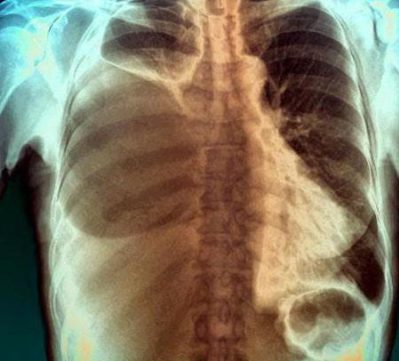

Для этого используется специальная тонкая стерильная игла. При плевроцентезе обязательно нужно соблюдать асептические и антисептические правила. Перед манипуляцией делается рентген грудной клетки.

При проведении плевроцентеза пациент не ощущает боли. Он может почувствовать только толчок в момент прокола грудной стенки. После манипуляции делается повторная рентгенография. Она нужна для убеждения, что плевроцентез проведен правильно и не задета легочная ткань.